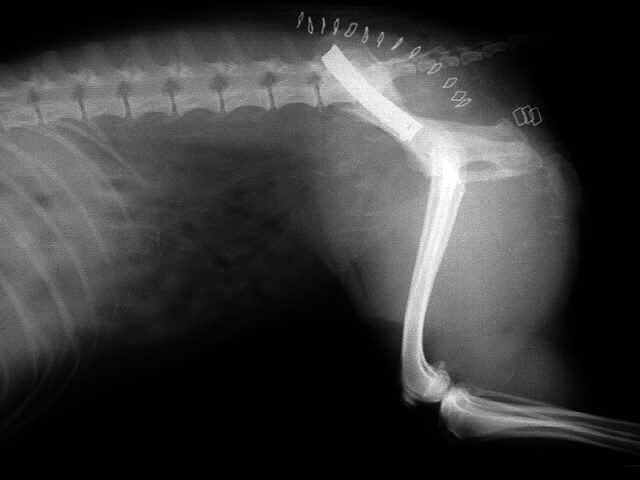

Hüftgelenksluxation

Toggle Pin - Anker - Fixation

Lendenwirbelfraktur L6

Fixation der Wirbelsäule mittels Querverbolzung durch beide Darmbeinflügel und Kreuzbein,

Drahtcerclage zwischen L6 und L7